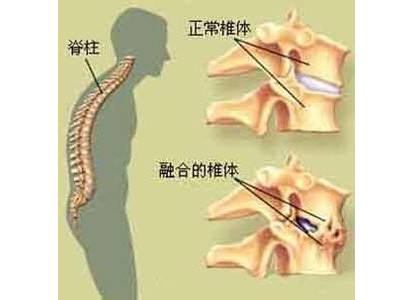

强直性脊柱炎以骶髂关节和脊柱附着点炎症为主要症状的疾病。与HL ...

强直性脊柱炎,是一种原因不明的、以中轴关节慢性炎症为主的全身 ...